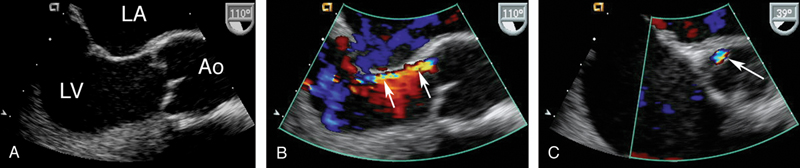

فحوصات تشخيصية لبعض امراض القلب والشرايين التاجية